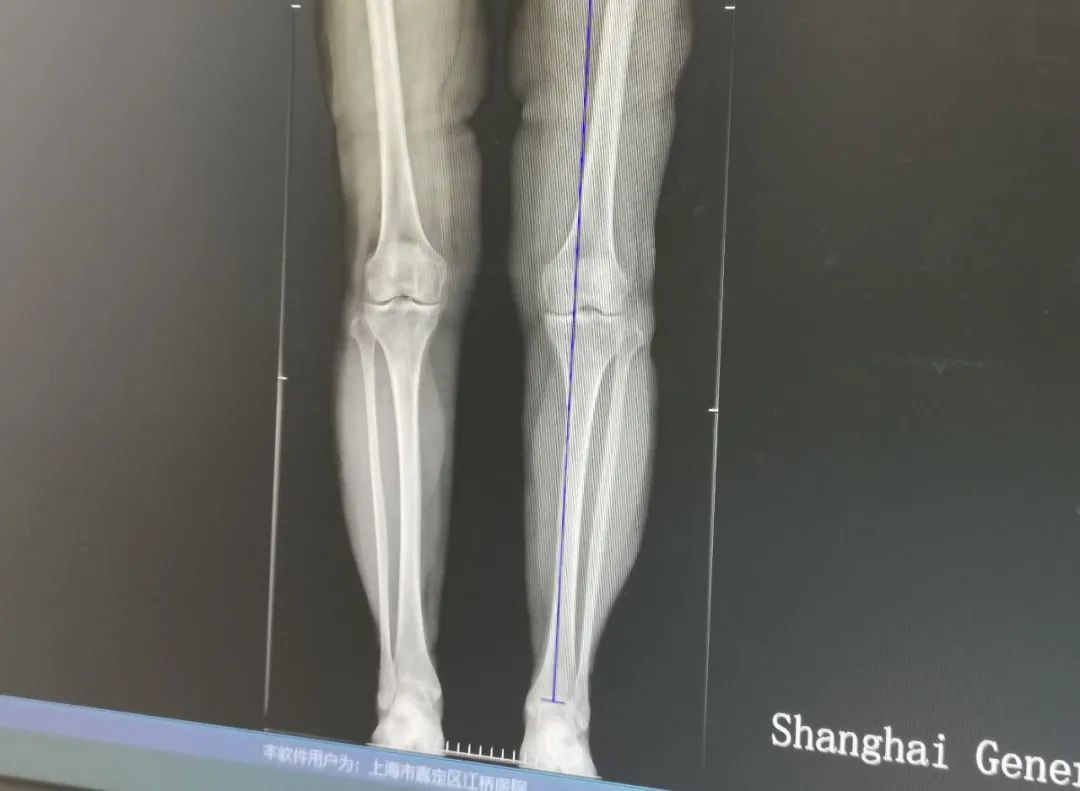

医生接诊发现,杨阿婆的关节炎已十分严重,并伴有一定程度的畸形,需要通过矫形手术来治疗。随后,医院骨科执行副主任孙健为杨阿婆进行截骨矫形微创手术。

孙健介绍,这类患者主要是因为膝关节内翻畸形或者外翻畸形,造成膝关节重心压迫到膝关节内侧或者内侧,而出现疼痛。

“长期压迫导致患者软骨损伤,通过截骨微创手术方式,让患者的力线恢复到正常的关节中心,减轻膝关节内侧或者外侧压力,从而治疗膝关节炎,这也是我们医院特色疗法。”孙健说。